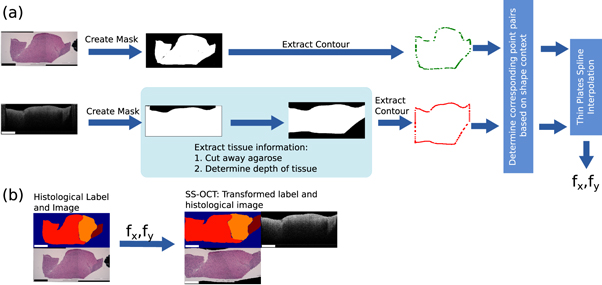

2.3.2. Label transfer from histology to the OCT images

This section deals with the second step of the workflow. It explains how the histological information in form of the delineated label was transferred onto the OCT images. The process will be described for the labels transfer onto the images of the SS-OCT images, but was analogue for the SD-OCT images. Figure 6 shows the processing pipeline of the label transfer.

Figure 6. Overview of the work-flow to find transfer the histological information onto the OCT image: (a) Determination of the displacement fields T between the OCT image and histological image. (b) Transformation of the histological label and image onto the OCT image with the displacement fields T. The rectangle in the bottom left of each image has the length of 1 mm.

Download figure:

Standard image High-resolution imageFigure 7. Depth of the agarose shape in the OCT B-scan varies with the axial position and thickness of the tissue due to differences in the refractive index along the depth axis.

Download figure:

Standard image High-resolution imageA transformation had to be determined for the transfer of the labels from the histology image onto the corresponding OCT image. The transformation is based on the outer shape of the sample. Due to the different image modalities and varying grade of details shown in the images, the use of intensity based features was not feasible. The outer shape of the tissue imprinted by the agarose hole is assumed to be similar in the OCT image and in the histological cut. The first part of the processing is the extraction of the tissue part from the histological image and the corresponding OCT image as binary mask which contain the information of the outer tissue shape. For the histological image the tissue was extracted based on the colour difference between the stained tissue and the white background. Locating and extracting the brain tissue in the OCT images took a few more steps: Each OCT image was processed through the already mentioned U-Net, which results in a binary mask. The columns of the mask were set to 0, if a column showed agarose in the original OCT image. The vertical margins were set manually by marking the left and right edge of the tissue in the OCT image, which was clearly distinguishable from the agarose. The pixel location of the bottom of the agarose imprint needed to be estimated, because the border between agarose and tissue was not visible due to the depth signal decay of the OCT image. This pixel location depends on the ratio of air and tissue. Since this ration changes over the OCT image, the location had to be determined for each image column. The axial pixel size Δs is scaled with the inverse refractive index of the medium n ( ). Figure 7 shows this effect unambiguously. If the agarose imprint is only filled with air (nair

= 1), the bottom of the agarose imprint appears higher in the OCT image whereas a composition of tissue (ntissue

> 1) appears lower.

). Figure 7 shows this effect unambiguously. If the agarose imprint is only filled with air (nair

= 1), the bottom of the agarose imprint appears higher in the OCT image whereas a composition of tissue (ntissue

> 1) appears lower.

The composition of air and tissue was determined from the binary mask. Since the composition of the brain tissue is unknown, it was assumed to have a constant refractive index of nt = 1.36 (Gottschalk 1992, Müller and Roggan 1995, Honda et al 2018). The actual depth d can be determined by the sum of all scaled pixel sizes:

Here z was defined as the axial pixel position within the image column. For each column of the binary mask pixels were set to 0 after the depth of the agarose imprint was reached. This results in a mask which marks the tissue content of the OCT image (figure 6).

After the extraction of the binary masks of the histology image and the OCT images, all masks were filtered by an edge filter in order to gain the mask outline, which essentially holds the outer shape information of the tissue. Each point of the mask outline has now a potential corresponding point on the other outline, which needs to be found in order to calculate the transformation between the two image modalities. For each point on an outline, a shape context feature was calculated (Belongie et al 2002). The shape context feature is a histogram-based descriptor, where the histogram describes the relative position of a point within a point cloud by a two dimensional histogram. In the first dimension the histogram bins describe the logarithmic spaced Euclidean distances log(r) from one point to all the other points of the silhouette. The logarithm was added in order to be more sensitive to close point position variations. Five bins were used from 0.125 to 2. Values smaller or bigger than the limits were assigned to the nearest bin. To achieve scale invariance, the Euclidean distance was normalized by the median distance between all the distances within one point cloud (Belongie et al 2002). The second dimension of the histogram describes the angle θ between the points, which was defined as the tangential angle between the point coordinates. Twelve bins were used ranging from 0 to 2π. To achieve some degree of rotational invariance, the angles were subtracted by the angle relative to the x-axis of the 1st principal component, which was calculated through the principal component analysis of the point cloud (Belongie and Malik 2000). The shape context features were determined for each point on the outlines. In order to identify the corresponding point pairs a linear assignment problem was solved based on the similarity of the feature histograms as described by Belongie et al (Belongie and Malik 2000).

The corresponding point pairs between two outlines were used to determine the transformation between the histological image  and

and  . An iterative thin plate spline interpolation approach was used for the determination in form of displacement fields

. An iterative thin plate spline interpolation approach was used for the determination in form of displacement fields  and

and  (Bookstein 1989, Belongie and Malik 2000). The displacements in x and y direction were calculated between corresponding points pairs of the histological image Phist

and the OCT image POCT

, which were interpolated to a displacement fields using the thin plate spline interpolation. The displacement fields fx,y

were described by the following equation:

(Bookstein 1989, Belongie and Malik 2000). The displacements in x and y direction were calculated between corresponding points pairs of the histological image Phist

and the OCT image POCT

, which were interpolated to a displacement fields using the thin plate spline interpolation. The displacement fields fx,y

were described by the following equation:

By using the histological contour points Phist

as supporting points and the displacement fx

(xi

, yi

) or fy

(xi

, yi

) between the corresponding points pairs of Phist

and POCT

, equation (5) can be solved for variables a1, ax

, ay

and wi

as described in Bookstein (1989) in order to gain the displacement for all the pixels of Ihist

. U(r) is a kernel function, which was defined as  . The displacement fields were then applied to the coordinates of the histological image x and y in order to map them onto the OCT image coordinates

. The displacement fields were then applied to the coordinates of the histological image x and y in order to map them onto the OCT image coordinates  and

and  .

.

The thin plate spline approach allowed the usage of a regularization parameter, which controls the stiffness of the transformation. The higher the regularization, the more the transformation resembles an affine transformation. Four iterations were used for the determination of the transformation. The regularization parameter was decreased with each iteration. The first iterations ensured an almost affine transformation for a general registration of the outlines, while the last iteration enabled an individual registration of the irregular outlines. The displacement fields from each iteration were then applied to the label of the histological section. Figure 6 shows an example of the transformation of the histological section onto the corresponding OCT image and the resulting transformed histological label.